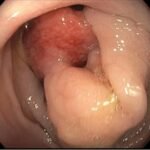

Intussusception is the telescoping of bowel into an adjacent segment of bowel and has an associated risk for bowel ischemia and perforation. The classic triad of abdominal pain, blood in stool, and an abdominal mass is present in less than 40% of pediatric cases and is less common in older children.1 Ultrasound has a high sensitivity and specificity for the diagnosis of intussusception, and once diagnosed, treatment modalities include reduction by either ultrasound or fluoroscopic guided air or hydrostatic enema. The risk of recurrence after successful reduction occurs in up to 12% of pediatric patients and occurs more frequently in older children and children with a pathologic lead point.2 We present a case of a 6-year-old child with colocolic intussusception that was successfully reduced and recurred within five days due to a large colonic polyp.